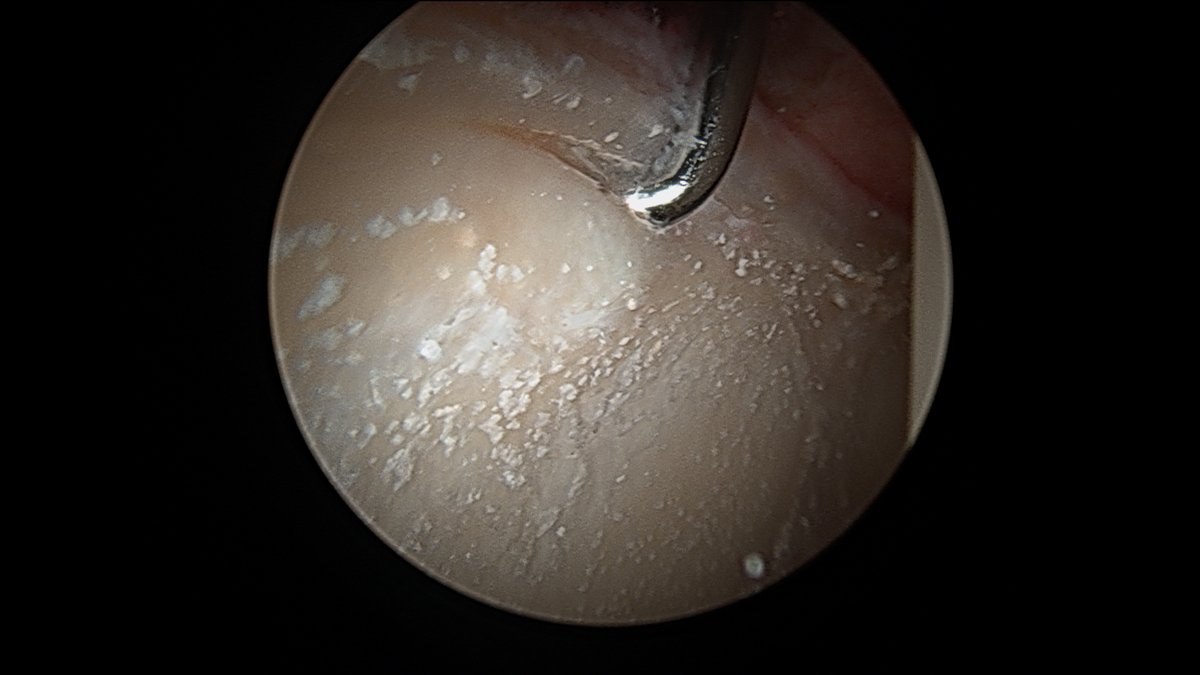

This is chondrocalcinosis isn’t it - not corticosteroid related ? 🤔

This is what a couple previous cortisone injections will look like during #hip #arthroscopy Interesting only on acetabulum, not on femoral head. Do you think these "crystals" (which, by the way, are almost impossible to get out without removing the cartilage) are a problem?